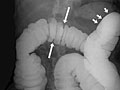

El enema de bario es una radiografía del intestino grueso (colon y recto). También se conoce como examen del tubo digestivo inferior. Esta prueba se utiliza para ayudar a detectar enfermedades y otros problemas que afectan al intestino grueso. Para hacer visible el intestino en una imagen radiográfica, el colon se llena con un material de contraste que contiene bario. Esto se hace vertiendo el material de contraste a través de un tubo que se introduce en el ano. El bario bloquea los rayos X. Esto hace que el colon lleno de bario se vea con claridad en la imagen radiográfica.

• En un estudio de contraste simple, el colon se llena de bario. Esto resalta el intestino y revela anomalías importantes.

• En un estudio de doble contraste o de contraste con aire, primero se llena el colon de bario y a continuación se drena el bario. Esto deja solo una capa delgada de bario en la pared del colon. El colon entonces se llena con aire. Esto proporciona una visión detallada de la superficie interior del colon. Hace que sea más fácil ver zonas estrechadas (compresiones), divertículos e hinchazón.

El enema de bario, o examen del tubo digestivo inferior, es una radiografía del intestino grueso (colon y recto).

Se detectan uno o varios problemas en el colon, tales como:

• Una sección del colon que no se llenó de bario.

• Un estrechamiento (compresión) en el intestino.

• Pólipos o crecimientos en la pared interior del colon.

• Sacos en la pared del colon ( diverticulosis).

• Problemas con anomalías e inflamación (colitis) del revestimiento del colon.

• Un segmento estrechado o un asa intestinal retorcida que está causando una obstrucción.

• Un intestino plegado en un niño, lo que es señal de invaginación. El enema de bario puede usarse como tratamiento para que el intestino vuelva a su posición normal.